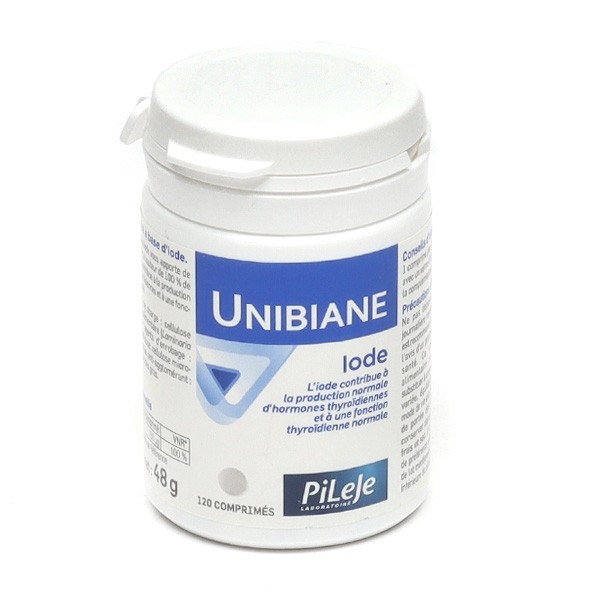

Gamme : Unibiane PiLeJe

Précautions d'emploi :

Ne pas dépasser la dose journalière recommandée.

Il est recommandé de demander l'avis d'un professionnel de santé.

Ce complément alimentaire ne peut se substituer à une alimentation variée, équilibrée et à un mode de vie sain.

A tenir hors de portée des enfants.

A conserver dans un endroit frais et sec.

A consommer de préférence avant fin et n° de lot mentionnés sur la face inférieure du pilulier.

| Valeur moyenne |

Par comprimé |

VNR* |

| Iode | 150 µg | 100 % |

Très bon produit qui permet de maintenir son taux d'iode.

Parfait

Trop tôt pour donner un avis. Je n'en suis qu'à 3 semaines de traitement.

Un peu tôt pour avoir un avis définitif. J'ai commencer à l'utiliser le 24 septembre, et je constate que mon taux de TSH s'est déjà amélioré. A confirmer.

Je ne sais que dire. Je pense que c est le genre de produit qui fait son effet sur le long terme